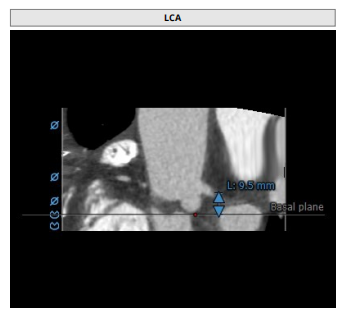

术前CT评估

瓣环:16.9mm,左室流出道:16.7mm

STJ:23.9mm,升主动脉:31.4mm

瓣叶增厚 右冠高度:10.9mm,左冠高度:9.5mm